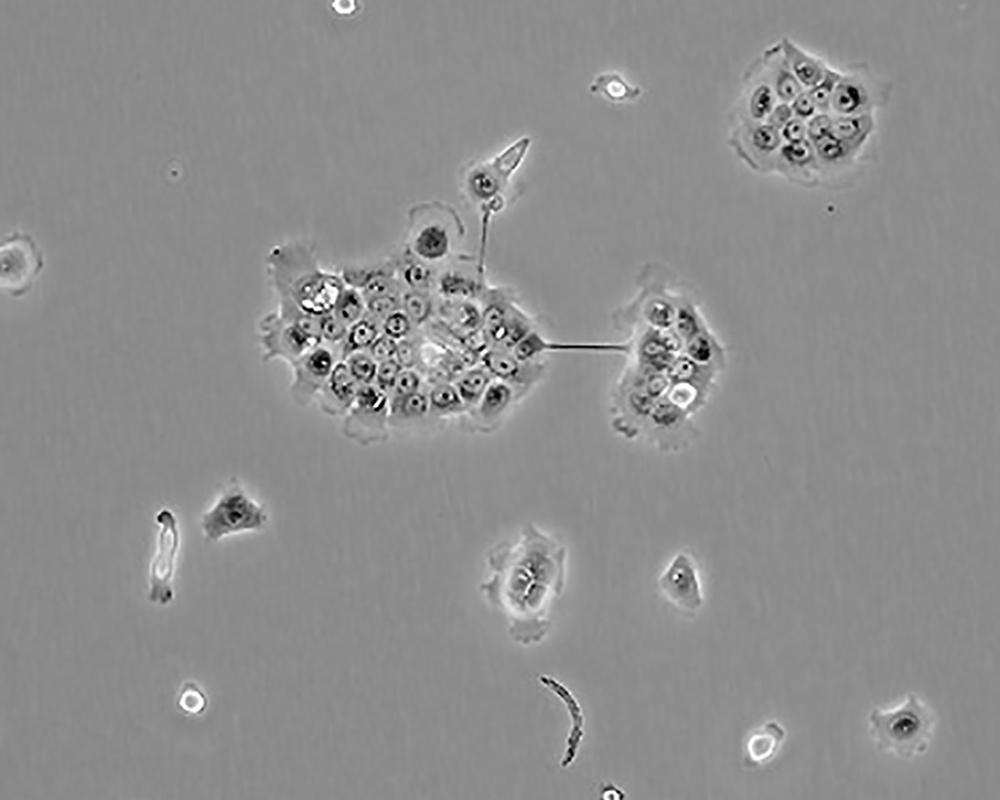

BxPC-3(BxPC3)

產品名稱 BxPC-3(BxPC3)

中文名稱 人原位胰腺腺癌細胞

組織來源 胰腺導管腺癌;女性

形態特征 epithelial